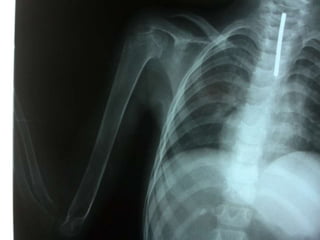

 3er semestre: Miembros inferiores y

dentición.

Radiología

 Deformidades , en forma de

incurvaciones o arqueamientos, en

especial en extremidades inferiores.

 Fracturas en tallo verde

Radiología  Deformidades, en forma de incurvaciones o arqueamientos, en especial en extremidades inferiores.  Fracturas en tallo verde